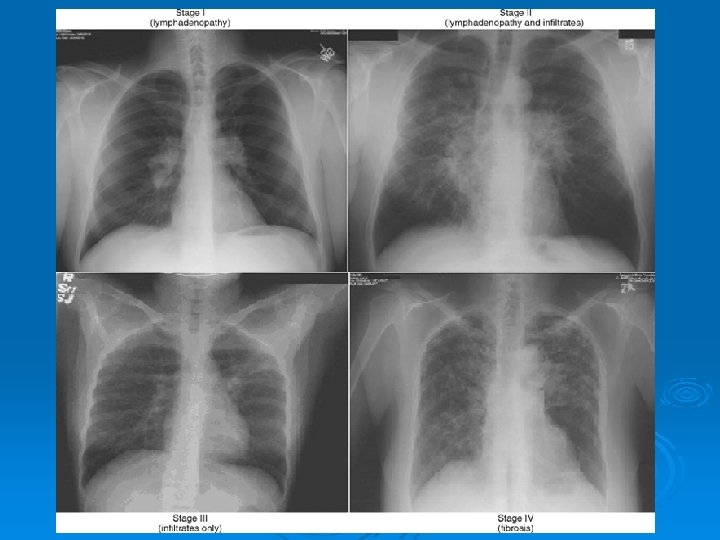

PA AKCİĞER GRAFİSİ Ø Grafiye göre evreleme yapılır: Evre 0: normal Ø Evre 1: bilateral hiler, mediastinal veya paratrakeal LAP Ø Evre 2: evre 1 + parankimal infiltrasyonlar Ø Evre 3: LAP ın eşlik etmediği diffuz pulmoner parankimal infiltrasyonlar Ø Evre 4: LAP ın eşlik etmediği fibro-kistik interstisyel akciğer hastalığı Ø

Stage I. Posteroanterior (PA) chest radiograph shows bilateral hilar and mediastinal adenopathy without parenchymal disease.

Stage II. PA chest radiograph demonstrates hilar and mediastinal adenopathy with fine nodular interstitial opacities.

Stage III. PA chest radiograph depicts diffuse bilateral reticulonodular opacities without lymphadenopathy.

Stage IV. PA chest radiograph shows fibrosis and upper lobe cystic changes and volume loss.